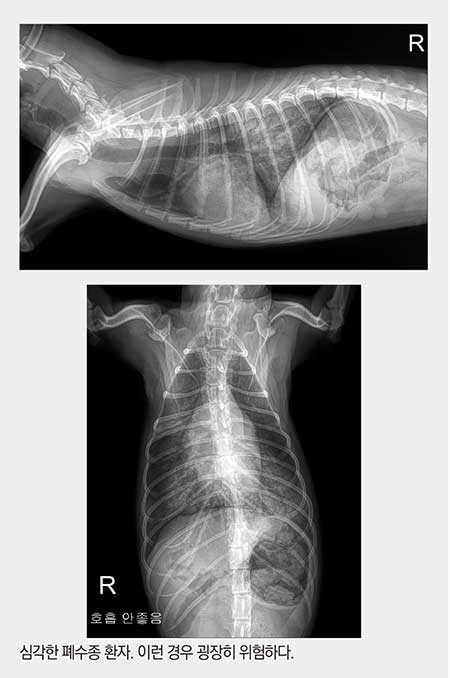

좌심실의 피가 좌심방으로 역류하고, 좌심방의 압력이 높아지면 폐울혈이 생기면서 폐에 물이 차게 된다. 물에 빠지는 것과 마찬가지 상태가 되어 호흡곤란으로 응급실에 내원한다. 운이 좋으면 약간의 폐수종 상태에서 “표정이 좀 이상해요, 간식을 안먹어요” 등의 증상을 호소하며 내원하지만, 어떤 아이들은 저산소증에 의해 곧 사망할 것 같은 상황으로 실려오기도 한다.

이런 경우 방사선 사진을 촬영하는 것조차도 위험해서 우선 iv 잡고 이뇨제 주면서 산소마스크를 쓰고, 호흡이 안정될 때까지(폐의 물이 좀 빠질 때까지) 기다린다. 병원까지 살아서 도착하는 것도 운이 좋은 경우에 속한다. 운명의 신이 병원에 오는 길에 아이를 데려가 버리기도 하니까.